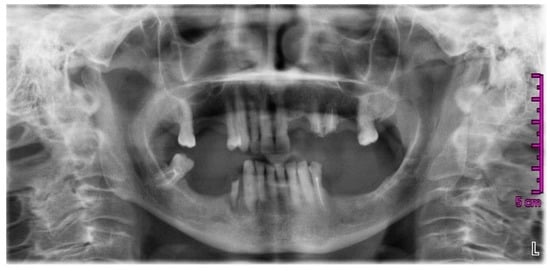

2. Case Report